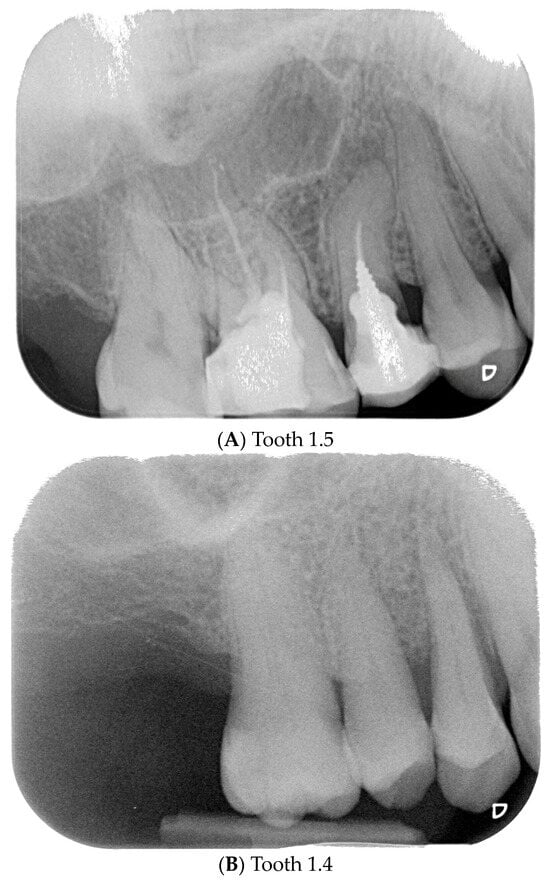

Figure 3.

Endoral RX prior to implant insertion: test group (A) vs. control group (B).

Preoperative examination addressed smile line, inter-arch relationship, and bucco-lingual bone thickness. Periapical radiographs and cone beam computed tomography (CBCT) were obtained to assess root dimensions, bone availability, adjacent structures, and implant planning. Preoperative periapical radiographs were taken using the VistaScan Mini Plus device (Figure 3) (Dürr Dental SE, Bietigheim-Bissingen, Germany).